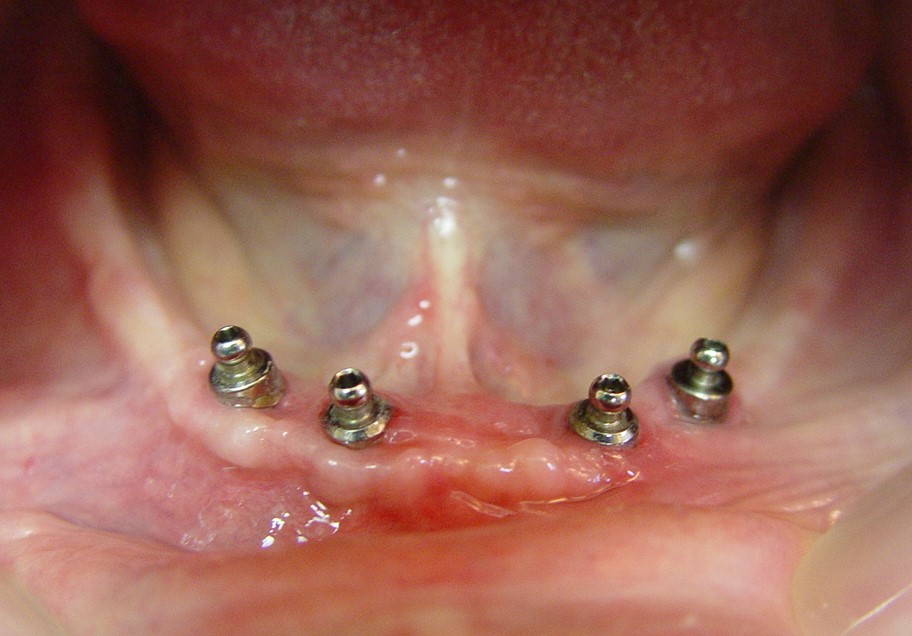

מבוגרים רבים מתפקדים במשך שנים עם שיניים תותבות, והתלונה העיקרית שלהם היא התותבת התחתונה:." לא יציבה, זזה, נופלת, אוכל נתקע " וכו'. בלסת העליונה קיים ואקום בין התותבת לבין רקמות הפה, אך בלסת התחתונה בגלל מבנה הלסת הדומה לפרסה, תנועת הלשון, ופתח יציאת בלוטות הרוק, לא מתאפשר ואקום והתותבת בדרך-כלל לא יציבה. עם השנים קיימת נטייה של עצם הלסת להיספג עוד יותר כך שהתותבת יציבה עוד פחות. במקרים שכאלה ניתן לפתור את הבעייה בפעולה פשוטה של החדרת 4-2 שתלים לצורך עיגון התותבת ולעיתים אף ניתן להשאר עם התותבת הישנה אשר הופכת ליציבה הרבה יותר. אופי השיקום תלוי בגיל המטופל ובמוטיבציה שלו (אני יכול להעיד על עצמי שכבר ביצעתי פעולה כזו לגברת בת 95) התותבת הופכת ליציבה וכתוצאה מכך הביטחון והתפקוד משתנים ללא היכר. פעולה זו מהירה, זולה יחסית ומשפרת את איכות החיים בצורה מדהימה.

- 4 שתלים לעיגון תותבת